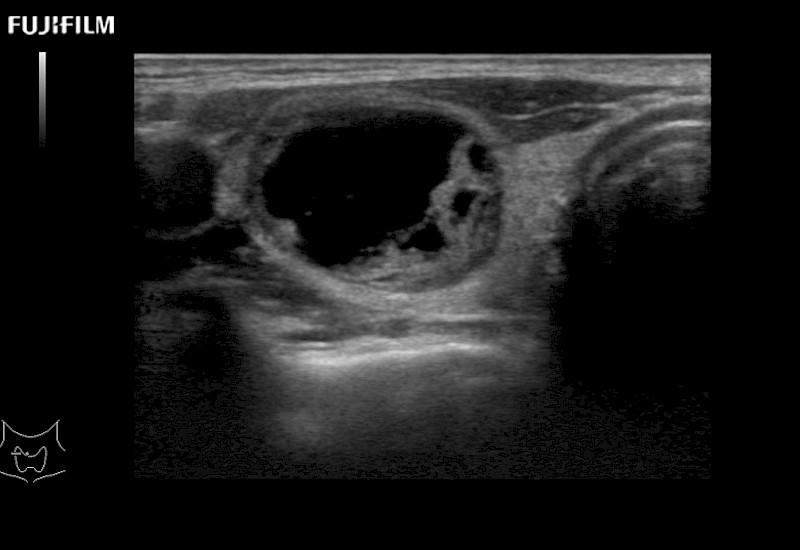

Our dedication to Surgical Oncology allows us to offer superior image quality, outstanding system reliability and intuitive use of cutting edge technology.